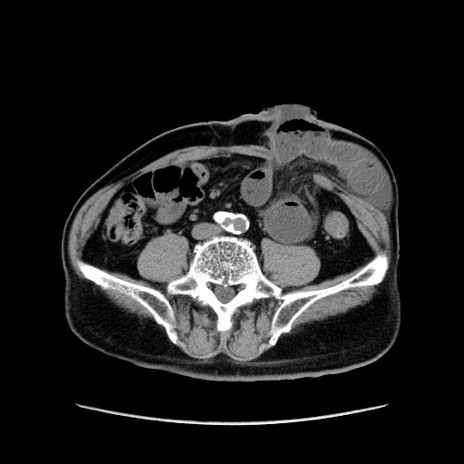

症例24(横断像)

【症例】80歳代男性

【主訴】左側腹部痛、嘔吐

【現病歴】本日早朝より左腹部に痛みあり。昼頃嘔吐認めたため、救急要請。

【既往歴】直腸癌(Mile手術)、胆摘

【身体所見】意識清明、BT 35.9℃、BP 221/93mmHg、SpO2 97%(RA) 、腹部:左ストーマ周囲に限局性の腹部膨隆あり。 膨隆部自発痛・圧痛あり・軟。

【データ】WBC 7700、CRP 0.09